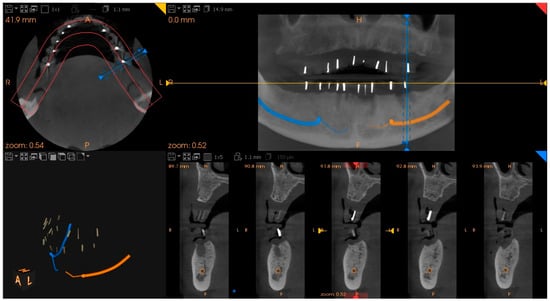

A cone–beam computed tomography (CBCT) scan was performed on the patient with the dentures in situ, providing visualizations of the gutta–percha markers and the alveolar bone’s anatomical dimensions (Figure 5).

Figure 5. CT scan showing the radiopaque gutta–percha cones inserted in the dentures, which mark the locations of the intended dental implants: voxel size 150, voltage 90 kV, current 4 mA, exposure time 15 s.